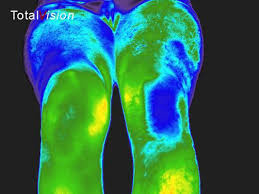

Vasculaire doorbloeding, spieren bij mens en dier en nachtzicht toepassingen.